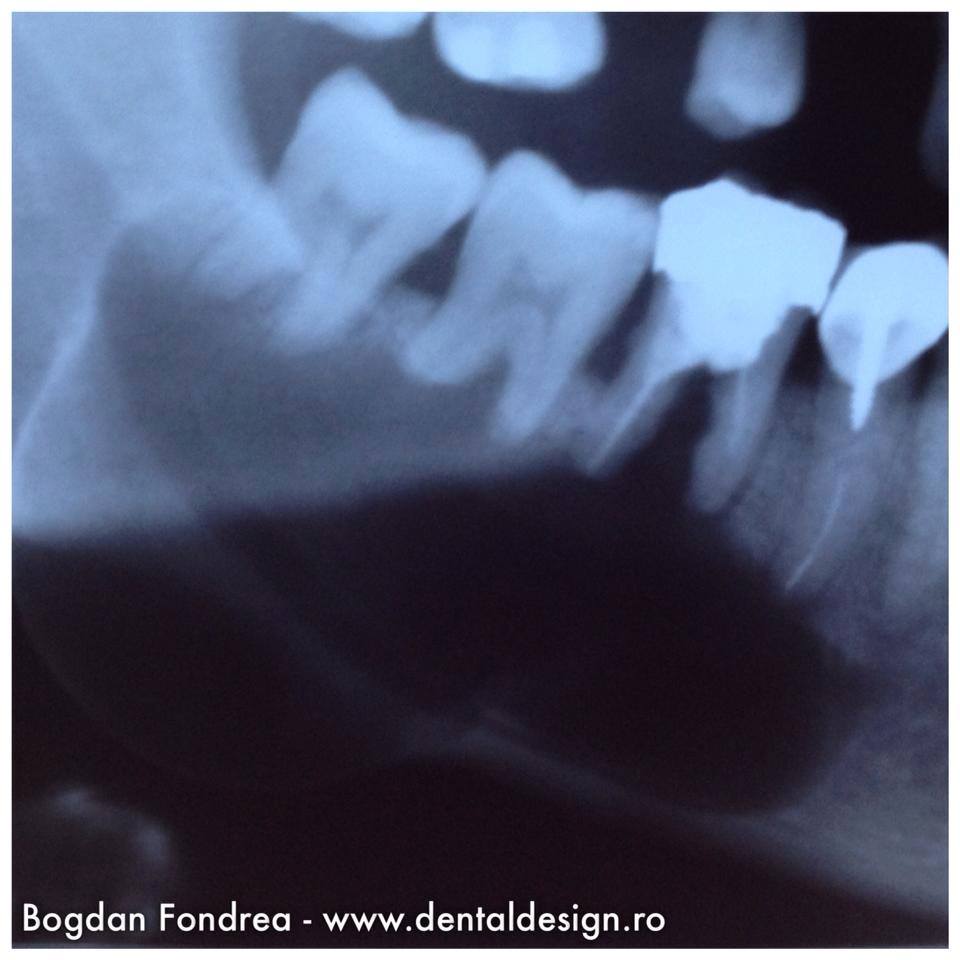

Cazul 2 – se poate vedea o infecție în os și se poate alege planul corect de tratament, plan ce este diferit de planul ce ar fi fost făcut fără radiografie. Așa s-a evitat o eroare grava de tratament.